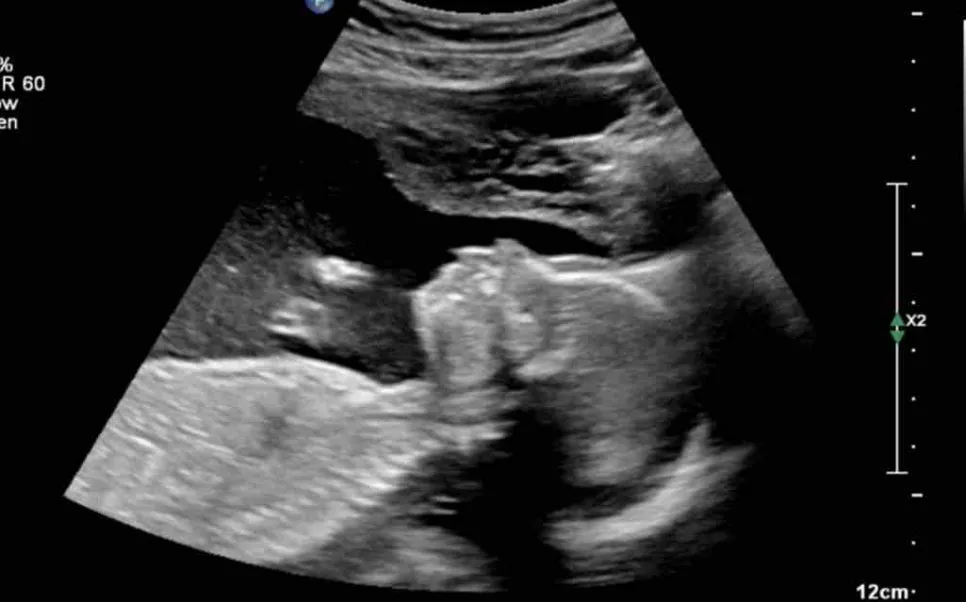

image.png?type=w966

주변에 아이가 생기지 않아 고생하는 사람들을 보긴 했지만 남의 일이라는 생각이 컸고, 자연임심으로 아이들을 낳은 친구들이 더 많았기에 나도 피임을 하지 않으면 어렵지 않게 아이가 생길 거라고 생각했다. 그러나 한 달 두 달이 지나도 소식이 없자 자연임신이라는 것이 쉬운 게 아니라는 것을 깨달았고 좀 더 집중해서 아이를 갖으려 노력한 결과, 세 달째가 됐을 때 마법처럼 생리가 멈추었다. 임신테스트기에 두 줄을 확인했을 때 심장이 두근거리고 호흡이 빨라졌다. 진짜인가 싶어 한동안 두줄을 뚫어져라 쳐다보고 있었다. 마이클은 이 소식을 듣고는 나를 안아주며 너무 좋다고 기뻐했다. 임신을 하고 나서 처음 몇 주 동안은 실감이 전혀 나지 않다가 12주 차 초음파에서 아기의 심장소리를 듣고 그제야 내 뱃속에 생명이 자라고 있다는 것을 느낄 수 있었다. 구토를 하는 입덧은 없었지만 4시간에 한 번씩 밥을 먹어야만 메슥거림이 줄어들었고 소화가 너무 안 돼서 항상 위가 불편했다. 먹지 않아도 메슥거리고 그렇다고 먹으면 또 소화가 안 돼서 아프고, 이도저도 하기 힘든 상태가 2달가량 지속됐다.